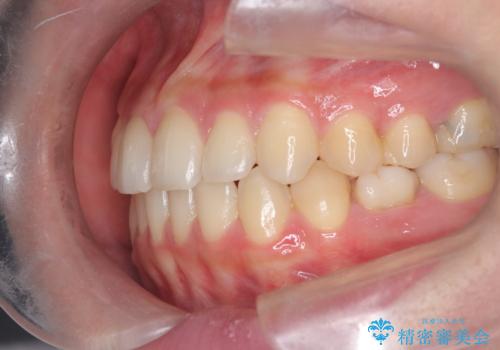

- 前歯の捻れを主訴に来院されました。

インビザラインを希望されておりましたが、20時間もつけることができなかったためワイヤー矯正にて叢生の改善を行っています。

右上の側切歯(前から2番目の歯)が90度程度ねじれている状態でしたが、1月に1回のワイヤー交換できれいに並ぶことができ満足いただけました。

捻れた歯の治療に関しては、ワイヤー矯正の方が仕上がりがきれいに治りやすいです。